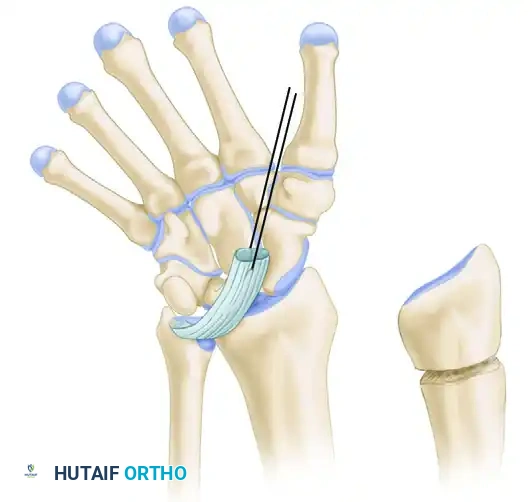

4. Osteotomy and Exposure of the Physis

Using a fine, sharp osteotome, make the initial longitudinal osteotomy in the radius. This cut should be parallel to the long axis of the forearm and positioned approximately 5 mm from the radioulnar joint.

Reflect the small, 5-mm fragment of the distal radius ulnarward using the osteotome. The goal here is to preserve what exists of the flimsy, attenuated connections between this fragment and the ulna, thereby leaving some critical soft-tissue support for the lunate and the DRUJ.

Once this fragment is reflected, a sagittal section of the distal radius should be clearly visible.

5. Physiolysis and Bar Resection

If the initial osteotomy is too shallow, you will observe a white sheet of fibrous tissue and cartilage. You must proceed deeper to locate the true physis.

Make successive, highly controlled osteotomy cuts, exactly 1 mm thick, moving radially and dorsally until the physis is clearly identified. When first visualized, the healthy physis will appear thin, wavy, and significantly narrowed compared to a normal growth plate.

Once the physeal cartilage is clearly defined, carefully remove the pathological bone from the metaphyseal side. This is best achieved using a fine gouge or a high-speed diamond burr under continuous saline irrigation to prevent thermal necrosis.

💡 Clinical Pearl

The resection must be meticulous. Remove bone so that the profile of the healthy cartilage sits above the surrounding bone. The cartilage must be left completely intact from the dorsal periosteum to the volar periosteum. Leaving any residual bony bridge will inevitably lead to a recurrent tether and failure of the procedure.